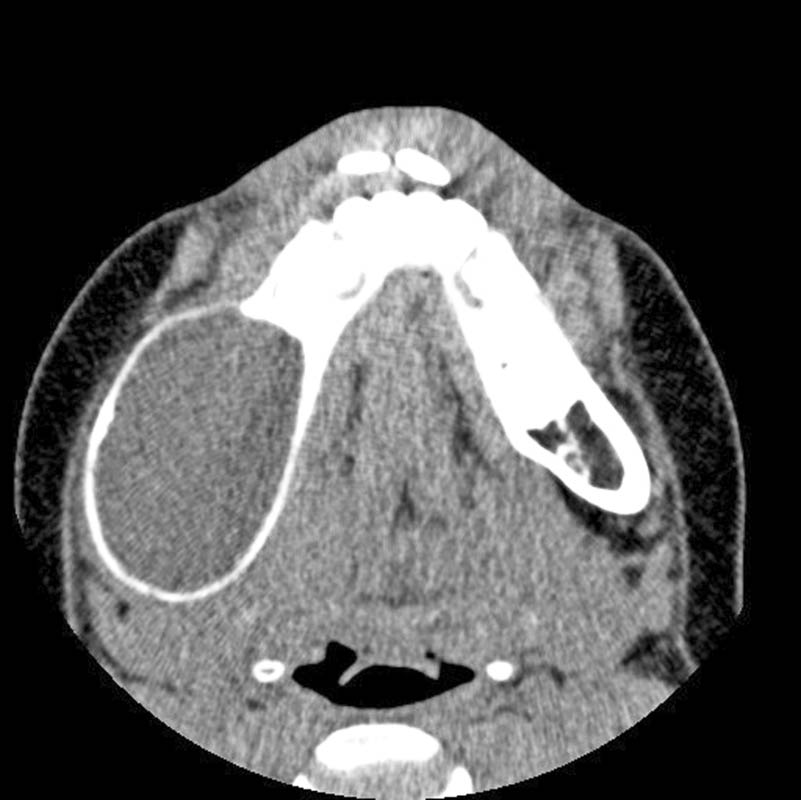

El caso clínico que presentamos es el de una paciente de 10 años derivada al Hospital Universitario La Paz por una lesión radiolúcida en el ángulo mandibular con abombamiento de las corticales. La biopsia confirma un diagnóstico de quiste odontogénico, que es extirpado, a la vez que se fija la fractura patológica asociada diagnosticada intraoperatoriamente. A los 15 meses, se observa una lesión radiolúcida, que se trata de forma conservadora, evitando la pérdida de los premolares adyacentes. Tras la extirpación, se obtuvo un diagnóstico histológico de ameloblastoma. En el seguimiento, no se observan recidivas y se aprecia correcta erupción de los premolares conservados.